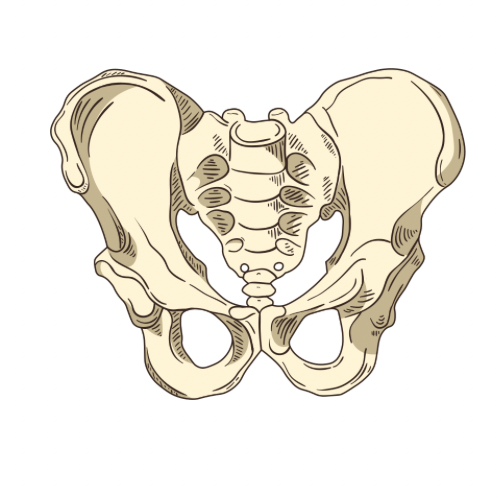

骨盤MRI

男性の場合

前立腺や精巣を観察します。

女性の場合

卵巣や子宮の観察をします。